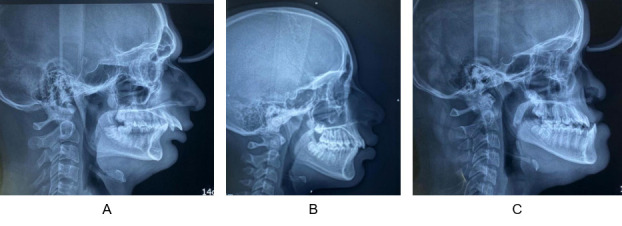

Materials and methods: 105 participants were equally divided as class I, class II and class III malocclusion based on ANB angle, Beta angle and Wits appraisal. The lip prints were recorded using lipstick cellophane method and were examined by Suzuki and Tsuchihashi method. For recording fingerprints, ink and stamp method was used and were analysed using Michael and Kucken method. Palatal rugae were marked on patients' maxillary casts and examined using the Lysell and the Kapali et al classification. To investigate the relationship between lip prints, fingerprints, palatal rugae, and skeletal malocclusions, the aforementioned values were all put through the Chi-square test.